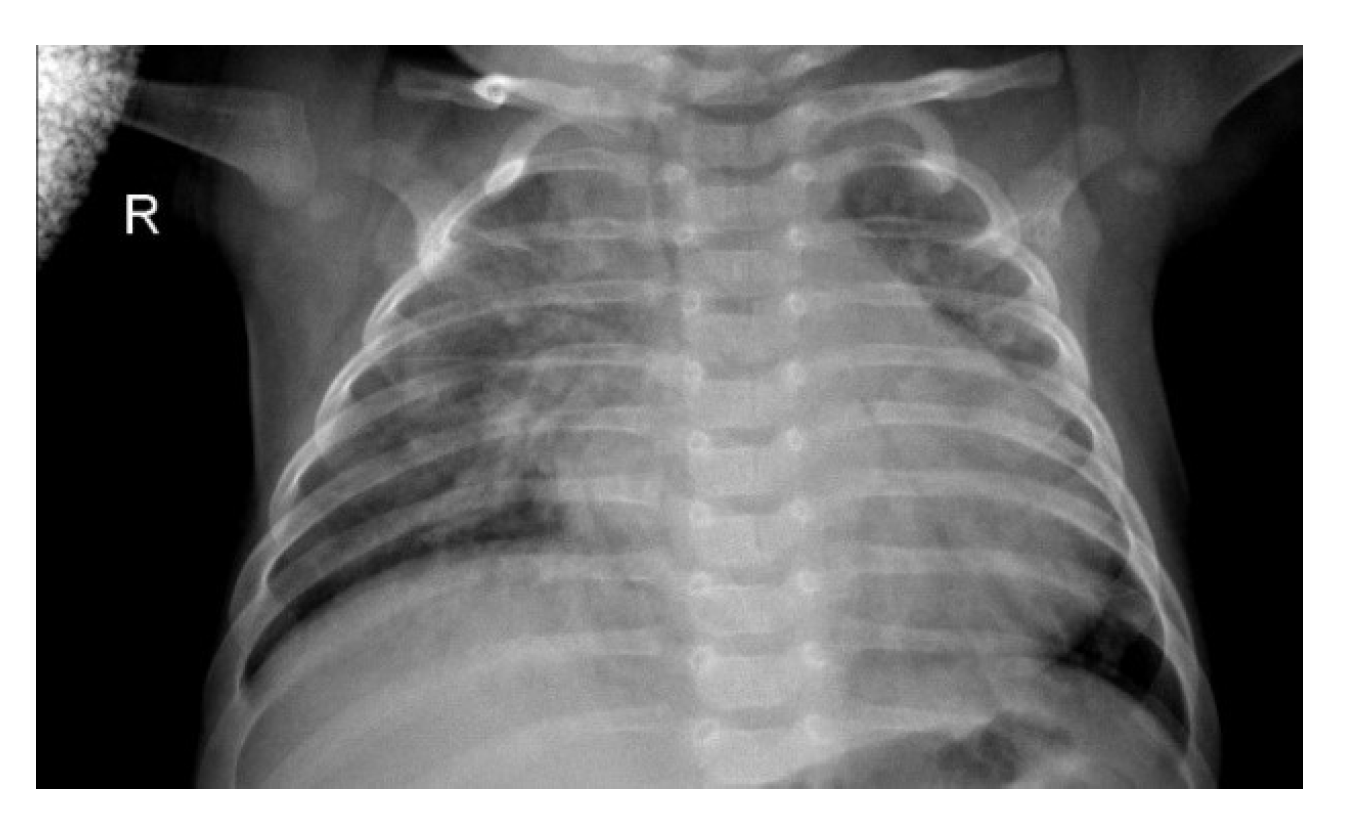

Figure 1.

Chest X-ray (CXR) image depicting pneumonia (as can be seen by inflammatory condition of lung).